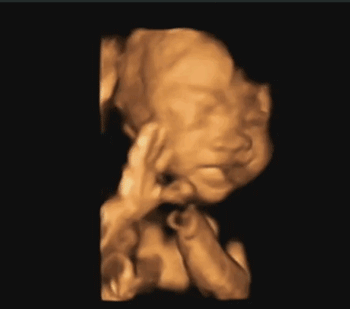

4.四维彩照只能看宝宝一举一动?

许多孕妈妈都很期待做四维彩超,因为这是准妈妈和胎宝的“第一次”见面,能够看到TA在肚子里或活泼或文静的可爱模样!但四维彩超更重要的作用是能够监测到胎宝宝的健康情况,进行排畸检查。

▶查看胎宝宝的活动

可以检查到胎宝宝在宫内是否缺氧,肢体运动、胎儿的吞咽动作等,能够很好地看到胎儿在孕妈妈体内的活动状况,说不定还可能看见宝宝做鬼脸、伸舌头哦。